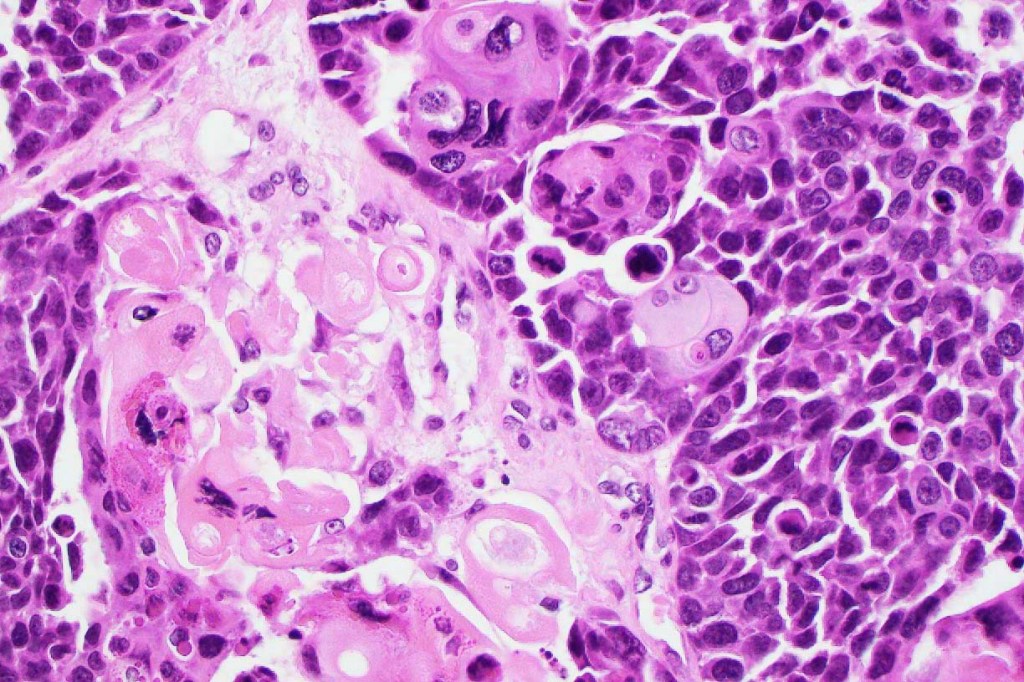

•Lobular or a diffusely infiltrating growth pattern. Composed of pleomorphic hyperchromatic, basaloid cells with nucleolar prominence, abundant mitoses & atypical mitoses (brisk mitotic activity should not be used as a defining feature of matrical carcinoma since in the evolving phase mitoses are typically very numerous in pilomatricoma)

•Necrosis common

•Matricial & supramatricial differentiation

•Clear cell change